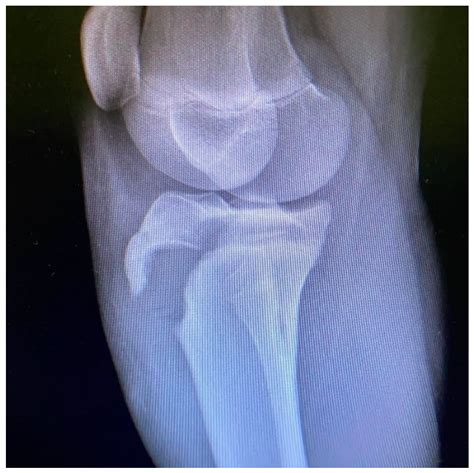

To confirm the diagnosis, medical professionals typically utilize imaging studies. X-rays are the gold standard for visualizing the displaced bone fragment and determining the severity of the fracture. In more complex or comminuted cases, an MRI may be ordered to assess the condition of the surrounding soft tissues, including the patellar tendon and menisci.

Orthopedic surgeons often categorize these injuries based on the Ogden classification system, which helps guide treatment decisions. This classification ranges from simple, non-displaced fractures to complex injuries that extend into the knee joint.

• tibial tuberosity fracture radiology